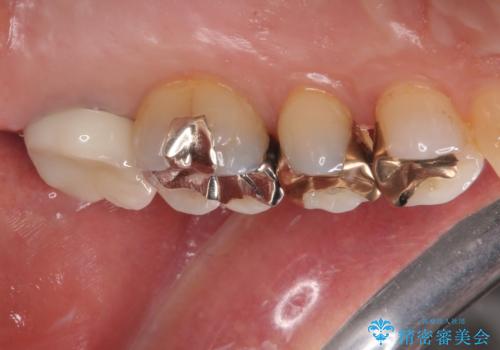

拡大鏡視野下で、金属の被せもの、虫歯の除去を行い、オールセラミッククラウンに適した形に整えました。

歯と歯茎の間に圧排糸と言われる糸を入れてシリコーン印象材にて型どりをしました。

患者様のご希望により、根管治療、土台のやり替えは行っていません。